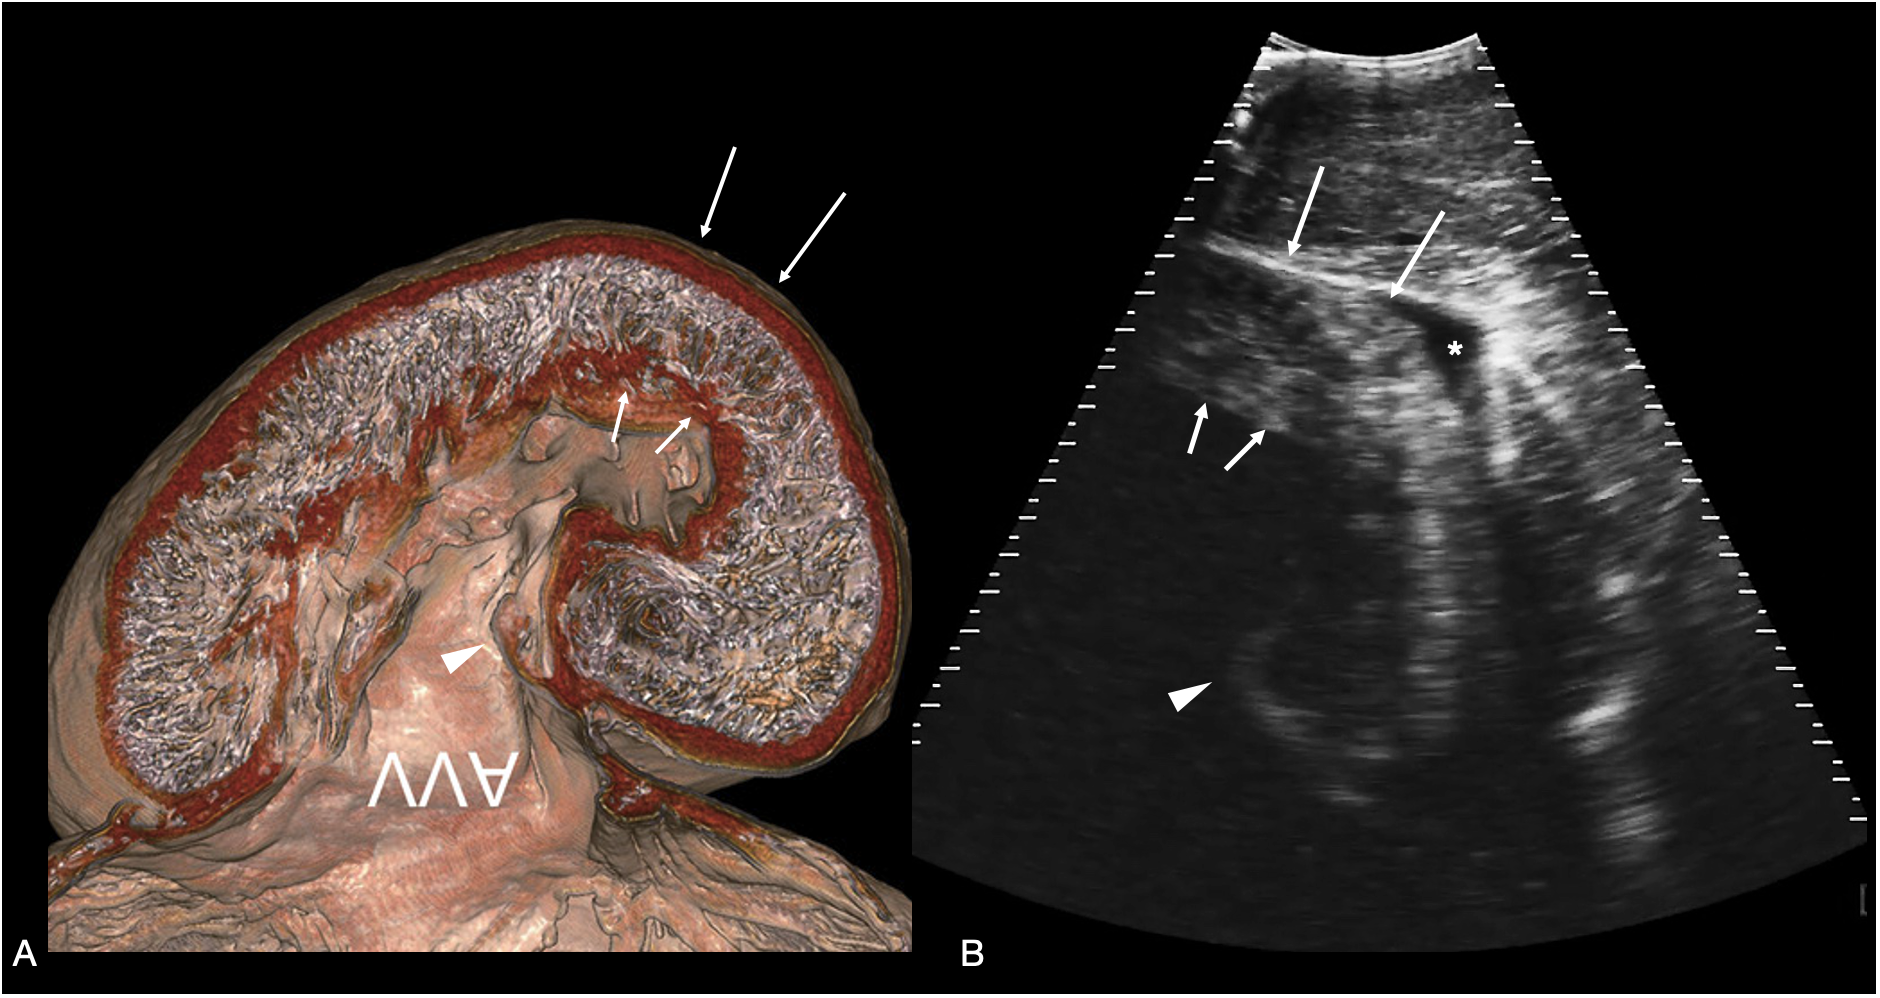

Figure 6

Atrioventricular valve. (A) Sagittal CT image of plastinated whale shark heart specimen reproduced from (Hirasaki et al., 2018) showing the ventricular myocardium and atrioventricular valve (AVV) - image inverted to correspond to the sonographic image. (B) Sagittal sonogram of the heart of whale shark 31 acquired on the ventral midline cranial to the pectoral line. The ventricular myocardium (arrows) and posterior leaflet of the atrioventricular valve (arrowhead) are clearly differentiated. In the near field (top of the image) is the hypaxial muscle of the ventral body wall, and a small volume of anechoic fluid surrounds the myocardium (marked *) within the pericardial space. The displayed depth is 21cm. See Supplementary Video S5.

Heart

The heart was readily identified cranial to the pectoral line, at midline. The ventricular wall thickness was ~4 cm during systole and ~2.5 cm in diastole. The atrioventricular valve was identified throughout its excursion (Figure 6). The thin-walled atrium was mostly beyond the extent of beam penetration, only partially visible beyond the valve annulus, and the sinus venosus was not visualized. Cranial to the ventricle, also on the midline, the conus arteriosus was identified as a funnel-shaped, muscular tube oriented in the sagittal plane (Figure 7). Sonographic anatomy was confirmed by correlating sonograms with published CT images of whale shark heart plastinated specimens (Hirasaki et al., 2018). When multiple heart contractions were observed a heart rate was calculated, and these ranged from 12 – 16 beats per minute.

We could reliably image the heart of a whale shark and monitor the activity of this organ. This revealed a heartbeat of around 12 - 16 beats per minute, a rate comparable to that of whale sharks imaged by ultrasound in aquaria (7- 18 bpm, K. Murakomo unpubl. data). Our sonograms captured the action of the ventricular contraction and atrioventricular valve motion (see video S5). It is not known whether heart rate variability would be a reliable indicator of health or stress in this species, however sonography may provide data for future research into this metric.